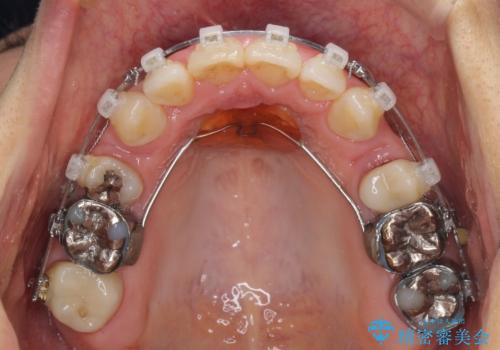

- クリアブラケット

- 3年4ヶ月

- 治療回数

- 30回以上

上顎左右第1小臼歯を抜歯したことで、隙間が閉じた下顎歯列の位置まで前歯を引っ込ますことができたため、口の閉じにくさを解消することができました。